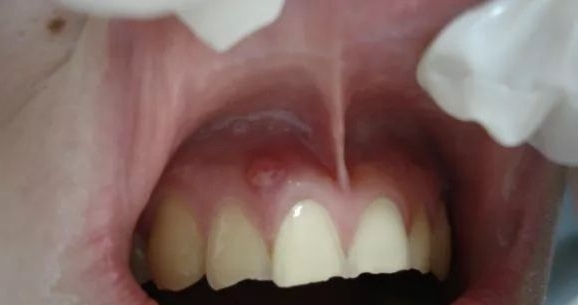

大家对牙龈上长脓包的情况已经见怪不怪了,吃东西的时候总觉得不舒服,总会摩擦到这个位置。如果没及时去处理脓包,它还可能越来越大而且越来越疼,连吃消炎药都不管用! 胆子大的忍不住把脓包戳破了,流出的脓液挺让人倒胃口,还会担心没有消毒会不会感染的问题。那么这脓包到底是怎么回事呢?为什么会反反复复呢?到底该怎么处理它呢?

今天“胡子叔叔”就带大家认识下这让人纠结的“脓包疙瘩”。除去一小部分的特殊原因,大多数的牙龈上长了脓包就代表着相应位置的牙齿出现了炎症问题。这就需要引起重视了。

你看到的只是表面现象,究其原因:一般情况是牙根炎症或牙龈炎症。

当蛀牙波及到牙髓的时候,细菌感染牙髓后慢慢繁殖引起牙根发炎,细菌感染牙髓演变成牙根炎症,引起牙槽骨蔓延,牙槽骨遭到炎症影响,所以牙龈上才会鼓起一个脓包,从根尖到牙根的瘘管,脓包内产生的分泌物由此流出。